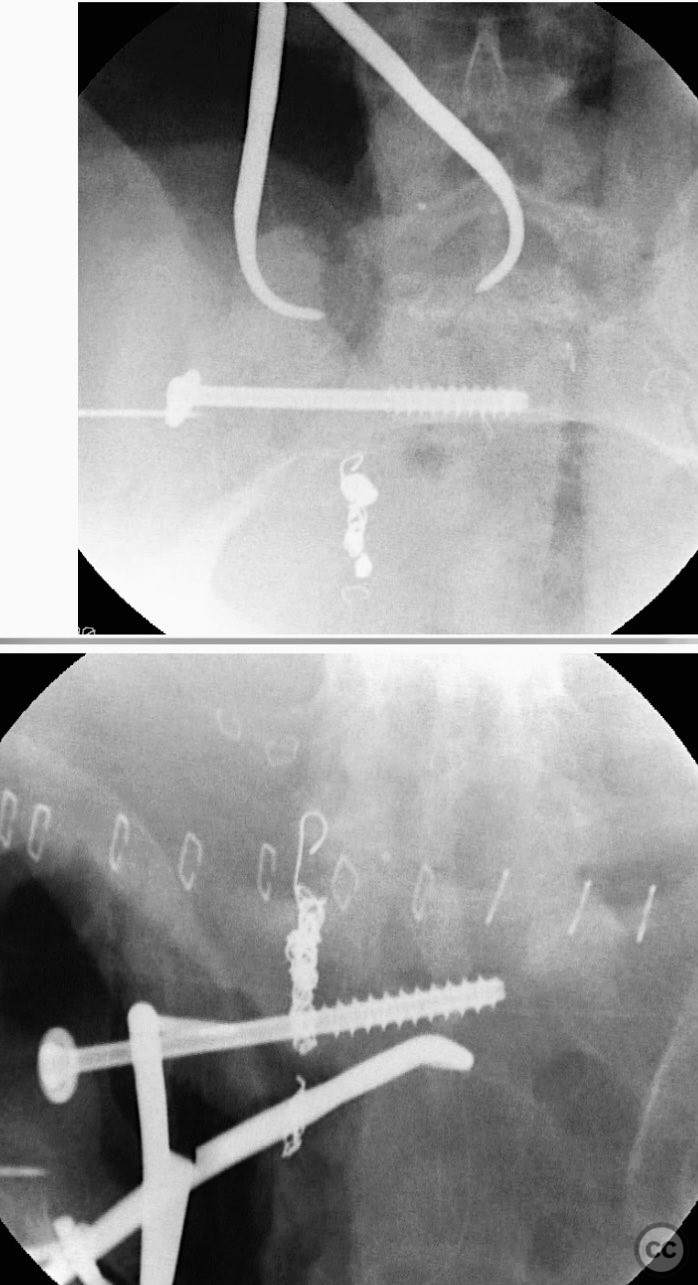

Clinical and radiological findings:  A 42-year-old male sustained a high-energy motor vehicle accident resulting in an unstable pelvic ring injury (AO/OTA 61-C1.3) with hemodynamic instability and associated intraperitoneal bladder rupture. Initial computed tomography demonstrated a complex anterior pelvic ring disruption and a posterior sacral fracture with contrast extravasation and blood within the fracture site. The patient was hemodynamically unstable on presentation.

Patient positioning:  For anterior pelvic fixation and bladder repair, the patient was positioned supine. For posterior sacral ORIF, the patient was repositioned prone.

Anatomical surgical approach:  The anterior approach utilized a Pfannenstiel incision to access the symphysis pubis and pubic rami, with subperiosteal dissection of the rectus abdominis and exposure of the retropubic space for reduction and fixation. For posterior sacral ORIF, a midline longitudinal incision was made over the sacrum, with subperiosteal elevation of the paraspinal musculature to expose the sacral fracture. A tenaculum clamp was applied for direct reduction, followed by percutaneous insertion of iliosacral screws under fluoroscopic guidance.

Operative remarks:

The case was notable for initial successful multidisciplinary management of both hemodynamic instability and intraperitoneal bladder injury, allowing for staged surgical intervention. Despite accurate anterior pelvic reduction and fixation, postoperative imaging revealed worsening posterior sacral displacement, necessitating subsequent posterior open reduction. The use of a tenaculum clamp facilitated direct anatomical reduction of the sacral fracture prior to iliosacral screw fixation. The presence of an embolic coil from prior angioembolization did not impede surgical access or hardware placement. This case demonstrates that initial anterior pelvic ORIF does not complicate or preclude subsequent routine posterior pelvic ORIF in complex unstable ring injuries.